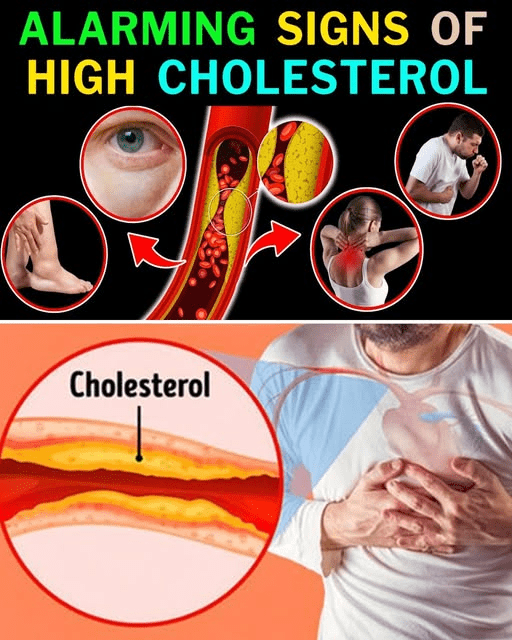

Artery blockages don’t appear overnight. They build slowly, quietly, and often without pain. That’s why many adults go years without realizing their arteries may be narrowing. The danger comes when cholesterol, inflammation, or plaque reduces blood flow.

The Countdown: Silent Signs You Shouldn’t Ignore

9. Unusual Fatigue That Doesn’t Match Your Day

8. Mild Chest Discomfort That Comes and Goes

7. Cold Hands or Feet, Even in Warm Weather

6. Jaw, Neck, or Shoulder Tightness

5. Shortness of Breath During Simple Tasks

4. Slow-Healing Cuts on Your Legs or Feet

3. Occasional Dizziness or Lightheadedness

2. Swelling in Your Ankles or Feet

1. Erectile Challenges in Men or Reduced Sensation in Women